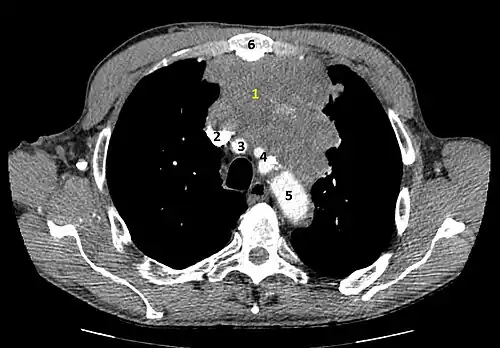

Scanner injecté, en fenêtre médiastinale, montrant un carcinome thymique envahissant les structures médiastinales :

1 : tumeur hétérogène, aux contours irréguliers, présentant des plages hémorragiques ;

2 : veine cave supérieure ;

3 : tronc artériel brachiocéphalique ;

4 : artères sous-clavière gauche et carotide commune gauche ;

5 : crosse de l'aorte ;

6 : sternum.- Scanner en fenêtre parenchymateuse, montrant un carcinome thymique envahissant les poumons (avec des lésions d'emphysème) au contact des deux poumons (1 : poumon droit ; 2 : poumon gauche) ;

flèches noires : zones suspectes d'envahissement.